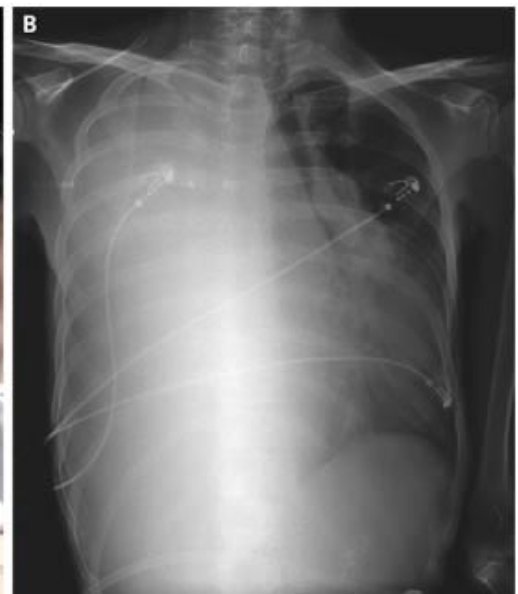

What is the diagnosis?

Cardiac tamponade

Tension hydrothorax

Diaphragmatic eventeration

Pulmonary hydatid disease

Lymphangiomyomatosis Image

Answer

Cardiac tamponade resolved after removal of 6 liters of pus from the right chest Image

A 43-year-old man

👉 respiratory distress after a 3-week illness

👉 h/o alcoholism but no other serious illness

👉 RR 34, HR 120 ,BP 80/50

👉oxygen saturation of 86% while breathing ambient air.

Read 13 tweets